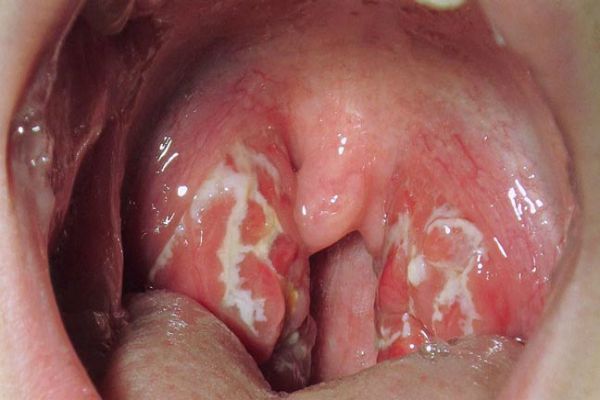

painful throat, PHARYNGITIS, STREP THROAT,EPIGLOTTITIS, sudden severe …

fever, headache, VERY SORE THROAT W/ SUDDEN ONSET, TONSIL ERYTHEMA and …

acid reflux symptoms in throat, strep throat symptoms adults, all of sudden sore throat, sore throat no other symptoms, pharyngitis symptoms, ,